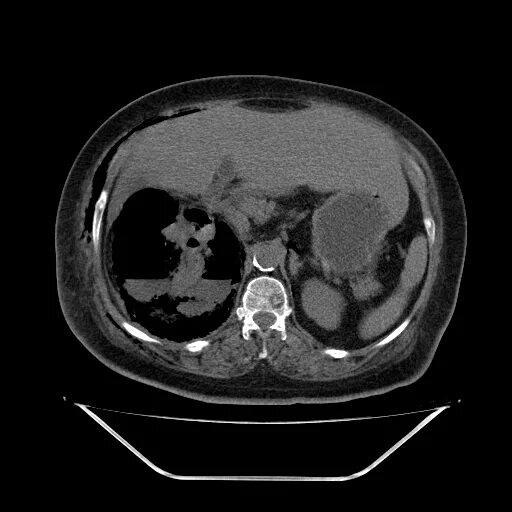

Пиелонефрит кт